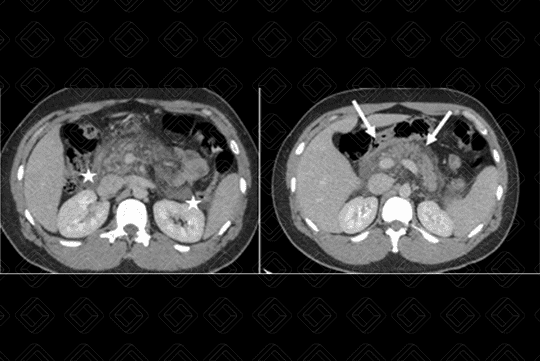

• Setas brancas evidenciam pâncreas de volume aumentado e densificação/infiltração da gordura peripancreática. Observar nos asteriscos brancos a presença de duas coleções fluidas no espaço pararrenal à direita e goteria parietocólica à esquerda.

• Duas ou mais coleções fluidas peripancreáticas (figura 2).